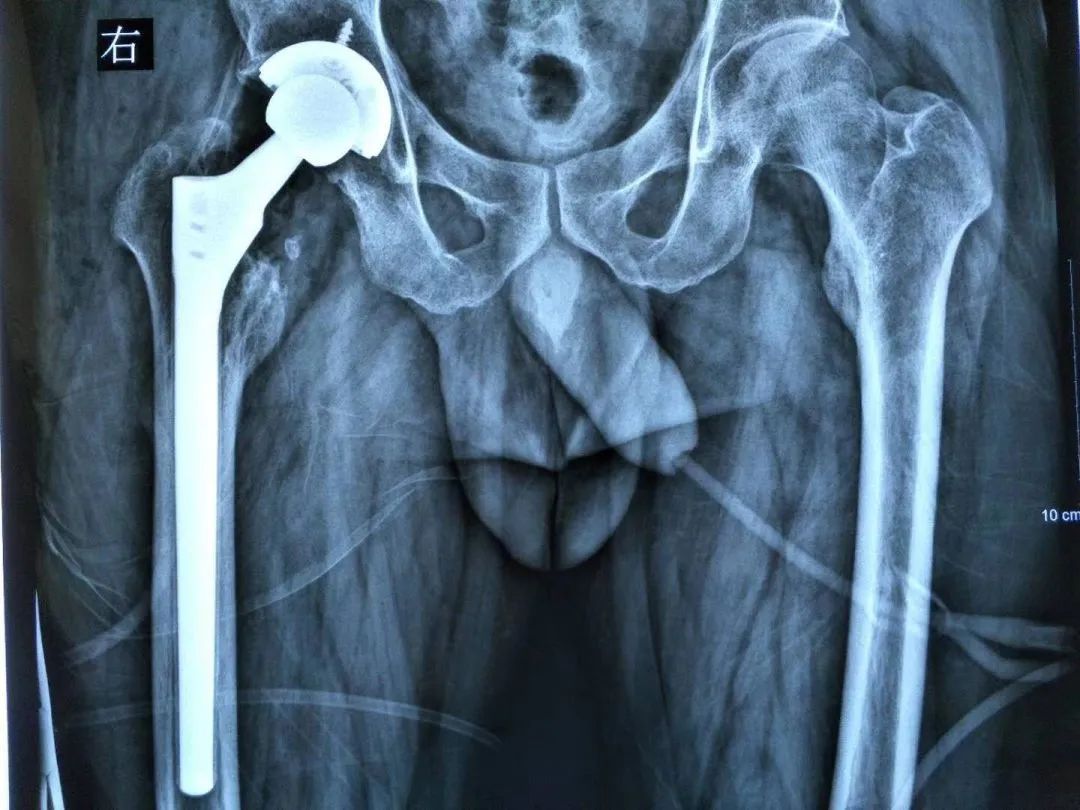

① 股骨侧:可以选择使用一体式的股骨翻修假体来恢复股骨的偏心距,这些假体在拥有多种偏心距可选外,还保持着相同的颈干角,进而能够灵活调整股骨偏距的同时,避免肢体过度延长(图1)。

图1 一体式翻修股骨柄